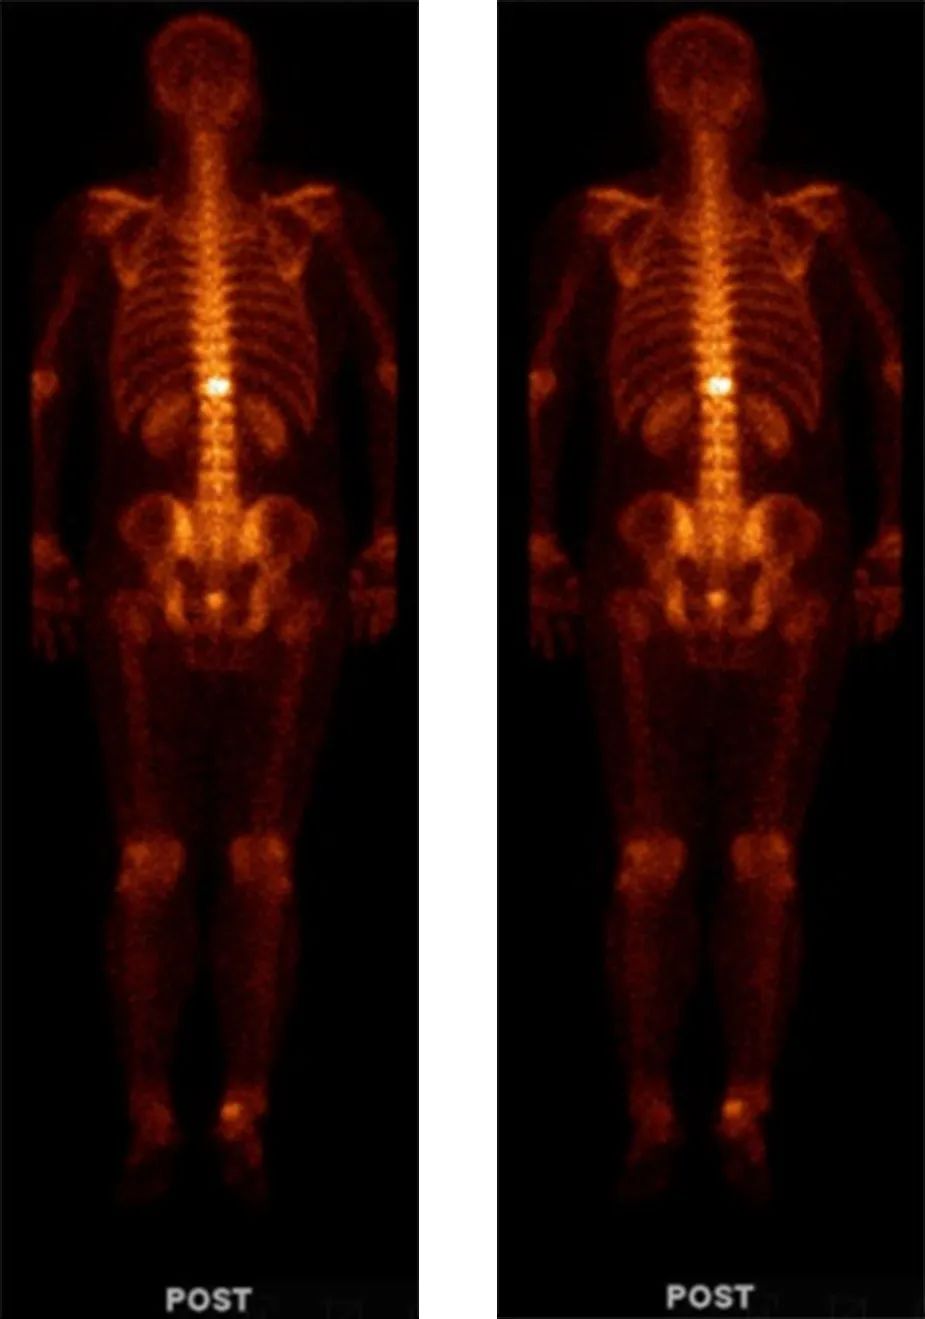

左:2017-01-25放疗后复查全身骨扫描;右:2017-07-15放疗后复查全身骨扫描

骨转移部位,病灶明显缩小,见下图,转移灶明显缩小

2018-04-19放疗后复查全身骨扫描